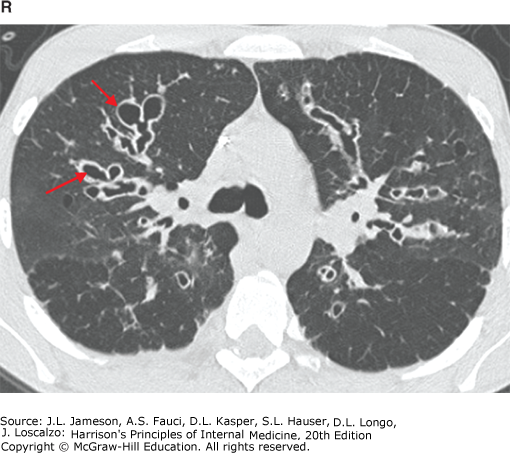

CT scan of diffuse, cystic bronchiectasis (red arrows) in a patient with cystic fibrosis.

C T scan shows cystic fibrosis. The red arrows point to diffuse, cystic bronchiectasis.